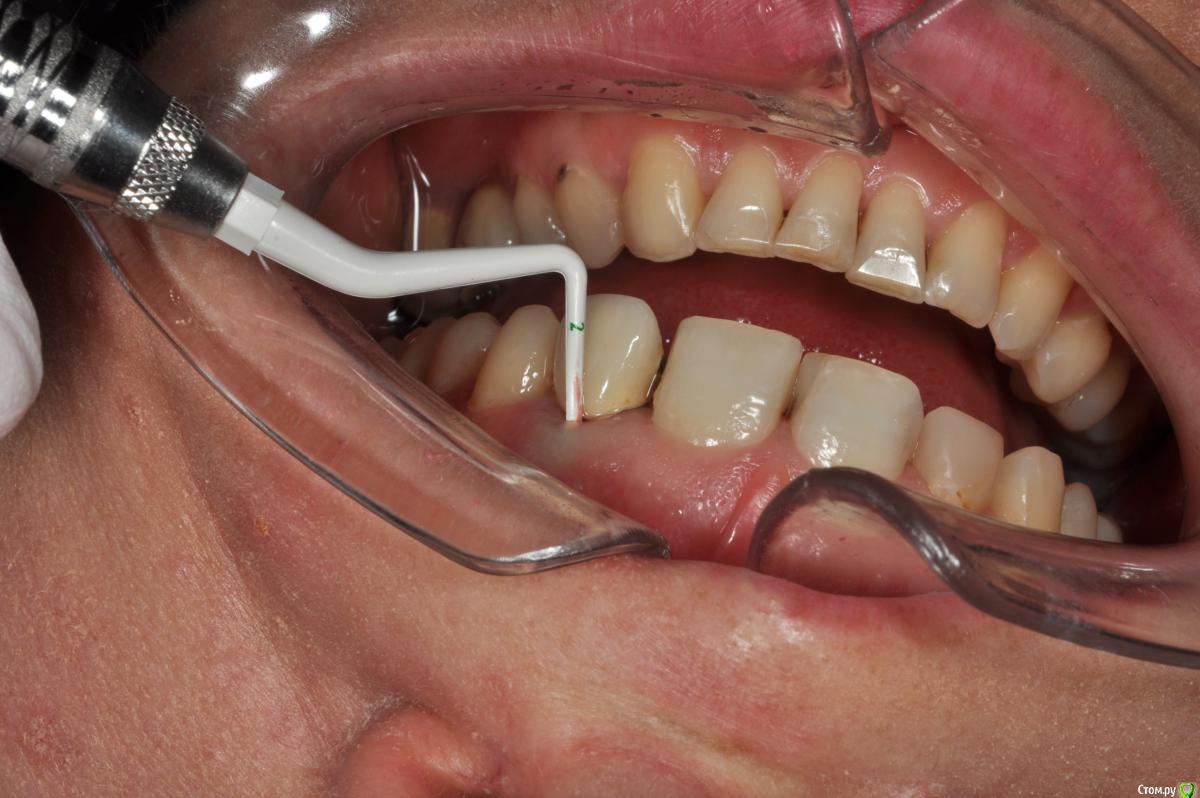

Пациентка 37 лет, не курит, соматически здорова. Частое выпадение ЛШКВ с коронкой. Диагностирована  фрактура вестибулярной стенки кореня зуба 22. Линия улыбки высокая. Биотип толстый.  Отсутствие вестибулярной пластинки, карман 8мм без ексудата.  Латеротрузия через 22.

Какая стратегия предпочтительней удаление корня 22, НКР, времянка понтик, потом имплантация с правельним наклоном. Или одномоментно с вестибулярным уклоном и в будущем  инд.абатмени+цементная фиксация.